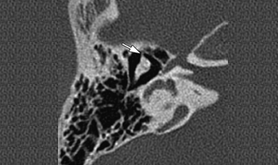

The temporal bone is a pair of bones on the sides of the human skull which houses the middle and inner ear. High Resolution Computed Tomography (HRCT) is highly effective in demonstrating the anatomy and pathology of the temporal bone. In order to obtain the proper diagnosis in infants and children, both the axial and coronal planes is taken utilizing HRCT.